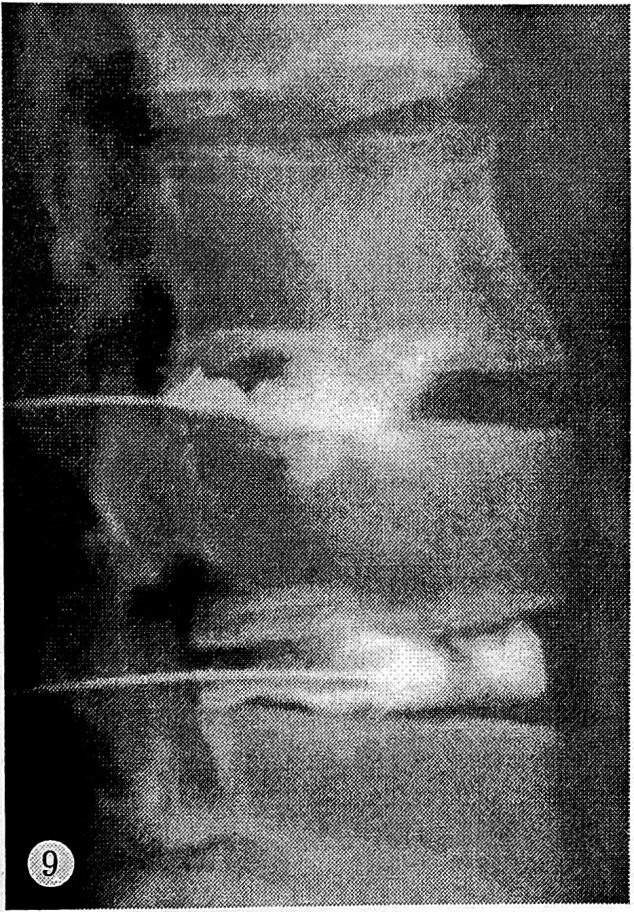

Субламинарный тип диСкограмм регистрировался в позвоночных сегментах с «чисто» клиновидными позвонками и позвонками с относительным увеличением переднезаднего размера тела. На дискограмме определялось контрастирование всех элементов диска с затеканием контрастного вещества под замыкательную пластинку через ее трещины и разрывы. Затекание контрастного вещества носило локальный характер и выявлялось как гомогенная линейная тень длиной не более 4—5 мм. Как правило, контрастировался прилежащий участок замыкательной пластинки. Отмечалось умеренное снижение высоты межтеловых промежутков (см. рис. 9). Емкость диска составляла 1,0—1,5 мл; его инъецирование сопровождалось поясничной болью средней интенсивности.

Рис. 9. Субламинарный тип дискограмм (контрастирование нижних замыкательных пластинок тел L2, L3 позвонков).